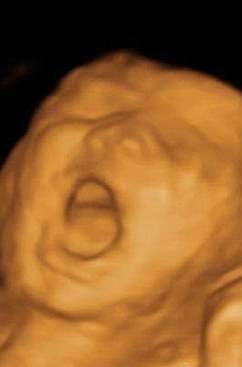

▼左边这个宝宝看起来正在大喊,右边这个宝宝则在思考人生。